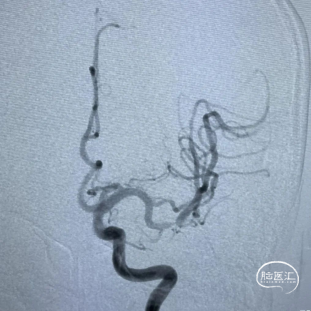

手术过程

患者全麻成功后,取平卧位于造影床上,选取右侧股动脉为穿刺点,按Seldinger法穿刺右侧股动脉,成功后置入8F动脉鞘。

长鞘在125cm造影管和0.035inch导丝辅助下,将长鞘带至左侧颈总动脉分岔处,将6F 125cm颅内支撑导管在0.035inch导丝辅助下超选至左侧颈内动脉岩骨段。

造影示:左侧大脑中动脉M2段管腔纤细、重度狭窄,测量狭窄约80%左右,远端血流缓慢,未见动脉瘤及血管畸形,拟行左侧大脑中动脉M2狭窄段球囊扩张开通支架植入成型术。

使用0.014inch微导丝塑形后辅助微导管通过左侧大脑中动脉狭窄段到达M3远端,造影确认微导丝在血管真腔,交换神经微导丝超选至左侧大脑中动脉M3远端。将6F 125cm颅内支撑导管在交换导丝及微导管支撑辅助下超选至左侧颈内动脉交通段,撤出微导管,交换加奇生物Fastunnel®输送型球囊扩张导管至狭窄病变血管处。

使用压力泵充盈Fastunnel®输送型球囊扩张导管扩张病变血管两次。造影见左侧大脑中动脉狭窄基本扩开。